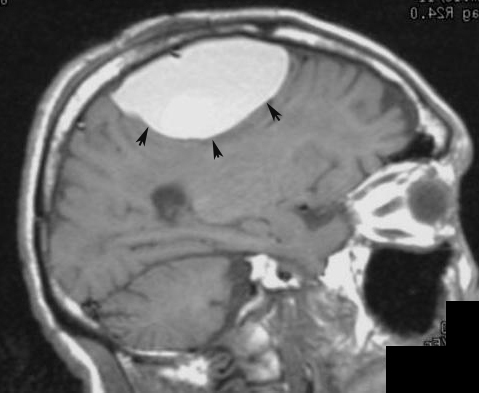

Radiology In Ped Emerg Med Vol 5 Case 7

Extradural Hematoma Subdural Hematomas Cerebral Contusions And Subgaleal Hematoma Radiology Case Radiopaedia Org